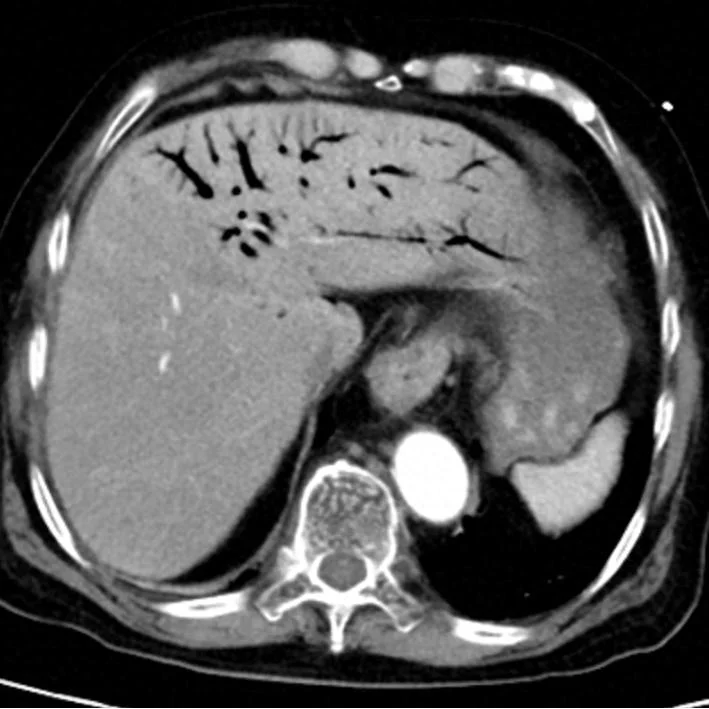

肝脏内血管广泛积气

腹胀明显,肠道积气